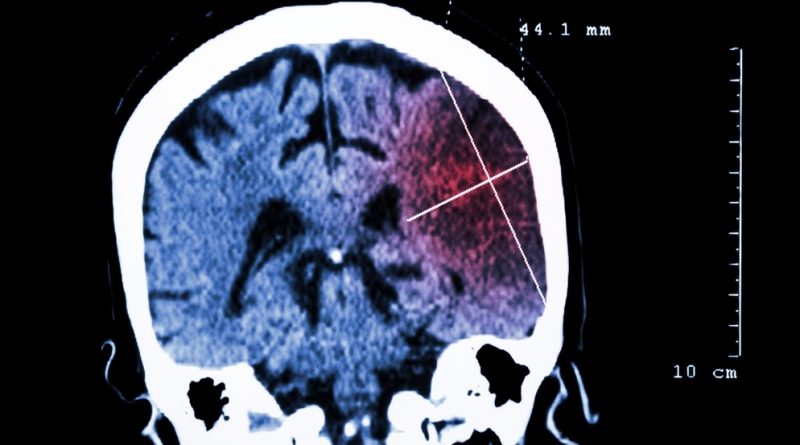

Un estudio indica que la muerte por ACV y las complicaciones circulatorias son más comunes en pacientes con COVID-19

Un nuevo estudio comprobó que la muerte por ACV y las complicaciones circulatorias son más comunes en los pacientes con el nuevo coronavirus. Se trata de un trabajo realizado por investigadores de la Universidad de Cornell, en el Weill Medical College, de Nueva York.

Publicada en la revista especializada JAMA Neurology, la investigación se realizó sobre 2.000 pacientes que llegaron al hospital New York-Presbyterian. En diálogo con MedPage Today, Neal Parikh, coautor del trabajo, dijo: “Aunque la tasa general de ACV en pacientes de COVID-19 fue baja, es sustancialmente más grande que la de los pacientes de gripe”. Y agregó: “Básicamente, nuestros resultados sostienen la idea de que la infección de COVID-19 es más grave que la gripe”.

“Según nuestro estudio, el riesgo relativo de accidente cerebrovascular isquémico es considerablemente mayor con COVID-19 que con la gripe, aunque el riesgo absoluto parece bajo en aproximadamente un 1, 6 por ciento”, dijo el Dr. Babak Navi, autor principal del estudio.

Los datos del estudio

Desde la página de Weill Cornell Medicine, explican que los investigadores encontraron que 31 (1.6 por ciento) de los pacientes con COVID-19, pero solo tres (0.2 por ciento) de los pacientes con influenza, presentaron un accidente cerebrovascular isquémico agudo o desarrollaron uno mientras estaban hospitalizados. Concluyeron que COVID-19 se asoció con un riesgo de accidente cerebrovascular isquémico 7,6 veces mayor en comparación con la gripe.

Los accidentes cerebrovasculares que ocurrieron en los pacientes con COVID-19 generalmente se limitaron a pacientes mayores (con un promedio de 69 años) y pacientes con factores de riesgo de accidente cerebrovascular conocidos, como hipertensión y diabetes. Los pacientes con accidente cerebrovascular tendían a tener la enfermedad COVID-19 más grave.